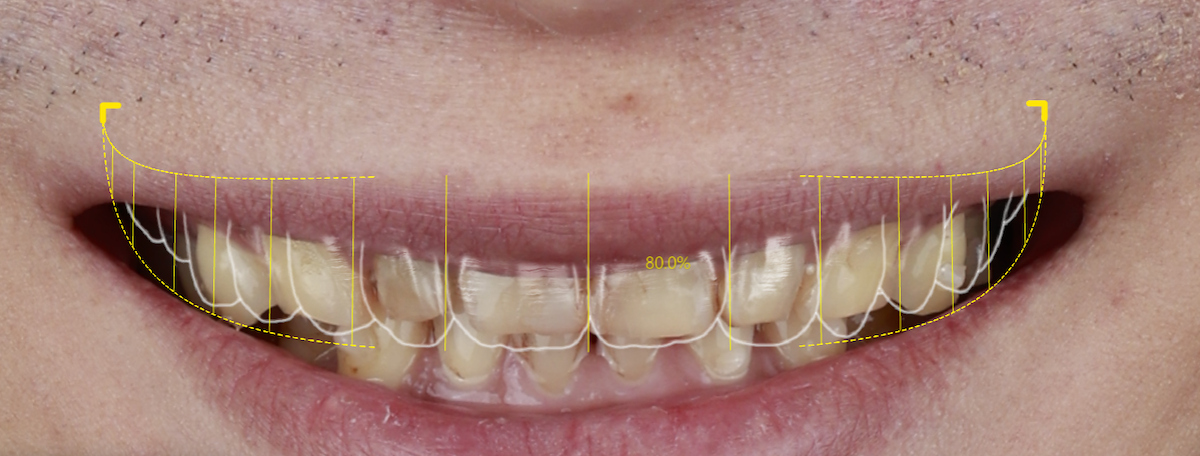

🔼 蒔美引進 DSD 微笑設計系統,讓患者在假牙製作前預覽未來笑容樣貌。再由數位牙體技術師同步製作臨時假牙,讓患者在實際試戴過程中,提前感受理想笑容的美觀與舒適,並根據李先生主觀感受進行微調,找到最終的完美方案。

Smile Introduces the DSD Smile Design System, Letting Patients Preview Their Future Smile. Digital dental technicians then create temporary prosthetics, allowing patients to trial their ideal smile and comfort. Adjustments are made based on Mr. Li’s feedback to achieve the final, perfected result.

華盛頓大學以美學為導向的全口重建理念(esthetically driven full-mouth rehabilitation),也在蒔美被完整實踐。團隊在規劃初期就先模擬出最理想的笑容樣貌,並透過高階DSD微笑設計系統,醫師、病患、技師三方緊密確認,讓每一步都精準銜接、事半功倍。任何治療細節都緊扣最終目標,恢復完美笑容的過程,不走冤枉路,也讓患者安心無虞。

The University of Washington’s esthetically driven full-mouth rehabilitation philosophy is fully realized at Smile. From the very beginning, the team simulates the ideal smile and uses the advanced DSD smile design system to ensure close collaboration between dentist, patient, and technician. Every step aligns precisely, maximizing efficiency. Each treatment detail is guided by the ultimate goal, making the path to a perfect smile clear and reassuring for the patient.